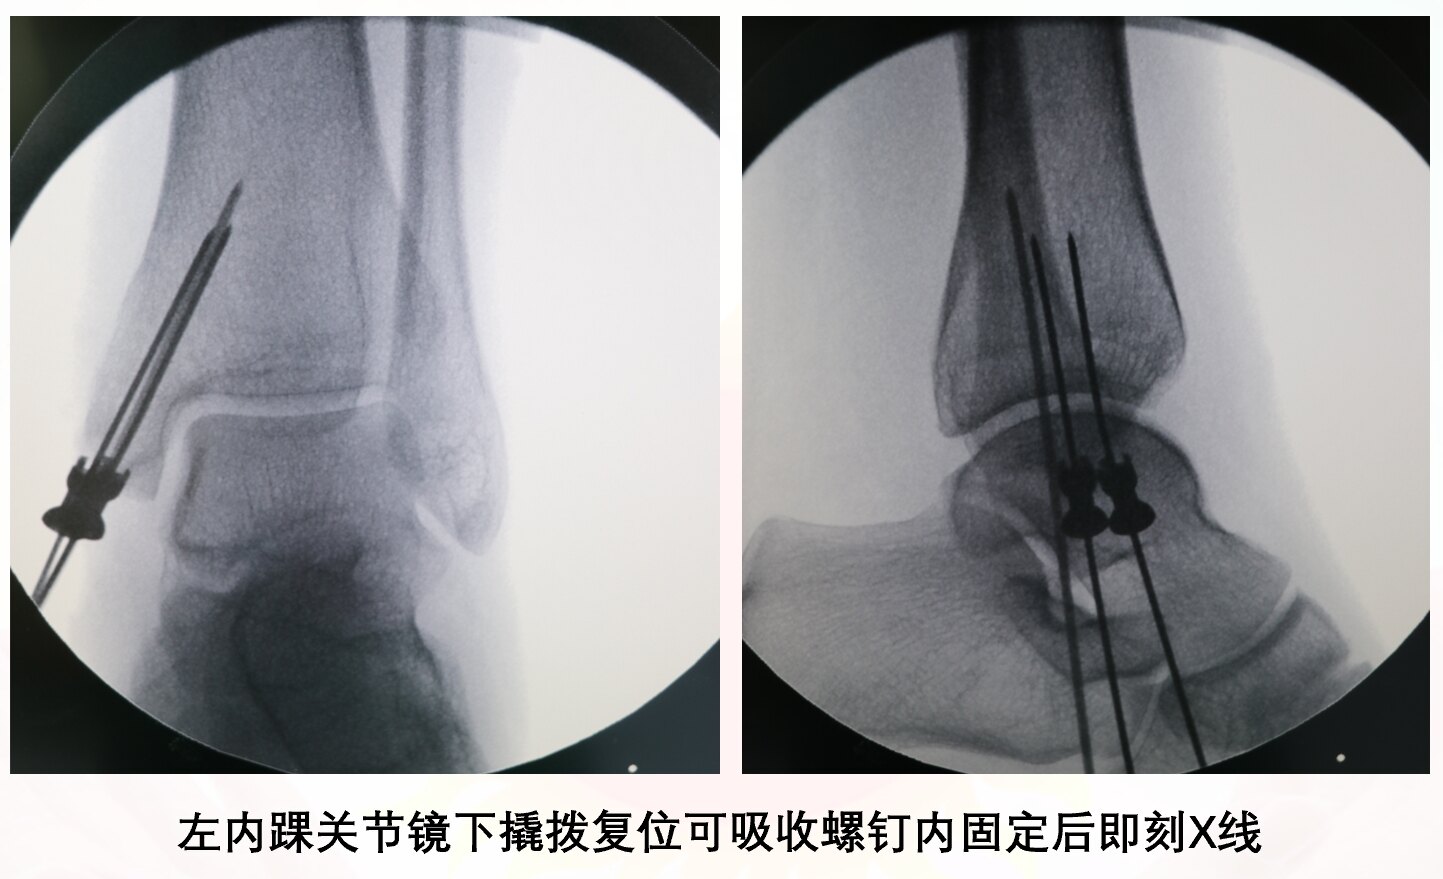

患者,女,33歲,因“騎電動(dòng)自行車車禍傷致左踝關(guān)節(jié)腫脹畸形1小時(shí)”入院,查體:內(nèi)踝前皮膚損傷(圖1),踝關(guān)節(jié)壓痛(+)。CT提示:左側(cè)內(nèi)踝骨折(圖2)。(病人車禍傷,基本醫(yī)療保險(xiǎn)不予報(bào)銷,自己購(gòu)買(mǎi)的商業(yè)保險(xiǎn)報(bào)銷)視頻1:術(shù)后3個(gè)月隨訪1.術(shù)后患者不用二次手術(shù)取內(nèi)固定物2.第二次取內(nèi)固定物的費(fèi)用與可吸收螺釘?shù)馁M(fèi)用相比,明顯少很多3.內(nèi)踝松質(zhì)骨血運(yùn)豐富,骨折愈合快,更易于可吸收螺釘?shù)氖褂?/p>